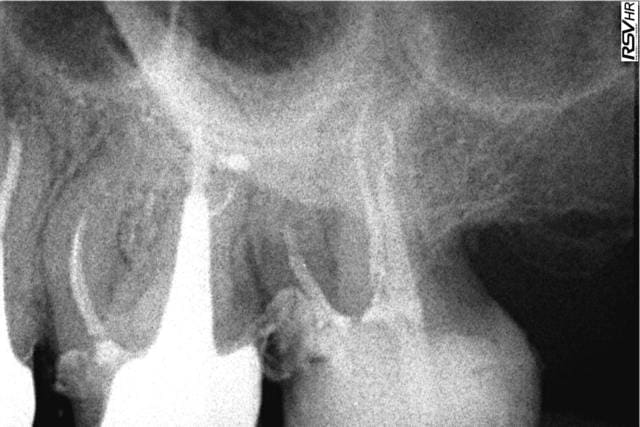

Voilà les radios : l'endo à l'amalgame dans la chambre de mon confrère (On notera aussi la belle endo sur la 6, courbure bien négociée par le confrère. Comment défendre ce type de boulot sur les 2 dents ?) et mon endo+RMIPP+compo à 139,70€.

Oui c'est pas au bout radiologiquement. A 80 ans c'est pas large, ça butait à la C+ 8/10èmes.

Le tenon fibré c'est la zone radioclaire au dessus, noyé dans le composite. On voit qu'il n'y a pas de gutta ni de ciment qui débordent.